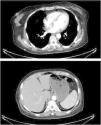

We present the clinical case of a seventy-year-old female patient with hypertension in treatment with olmesartan since one year ago and no other past medical history of interest. She was hospitalized in the internal medicine department in order to study constitutional symptoms which consisted of confirmed weight loss of 13 kg, chronic diarrhea, loss of appetite, asthenia, and intermittent colic-like abdominal pain. After an initial screening for neoplastic disease, other possible options were considered.